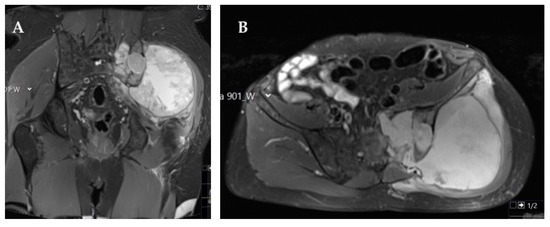

- Bloem, J.L.; Reidsma, I.I. Bone and soft tissue tumors of hip and pelvis. Eur. J. Radiol. 2012, 81, 3793–3801. [Google Scholar] [CrossRef]

- Rajiah, P.; Ilaslan, H.; Sundaram, M. Imaging of sarcomas of pelvic bones. Semin. Ultrasound CT MR 2011, 32, 433–441. [Google Scholar] [CrossRef]

- Park, S.K.; Lee, I.S.; Cho, K.H.; Lee, Y.H.; Yi, J.H.; Choi, K.U. Osteosarcoma of pelvic bones: Imaging features. Clin. Imaging 2017, 41, 59–64. [Google Scholar] [CrossRef]